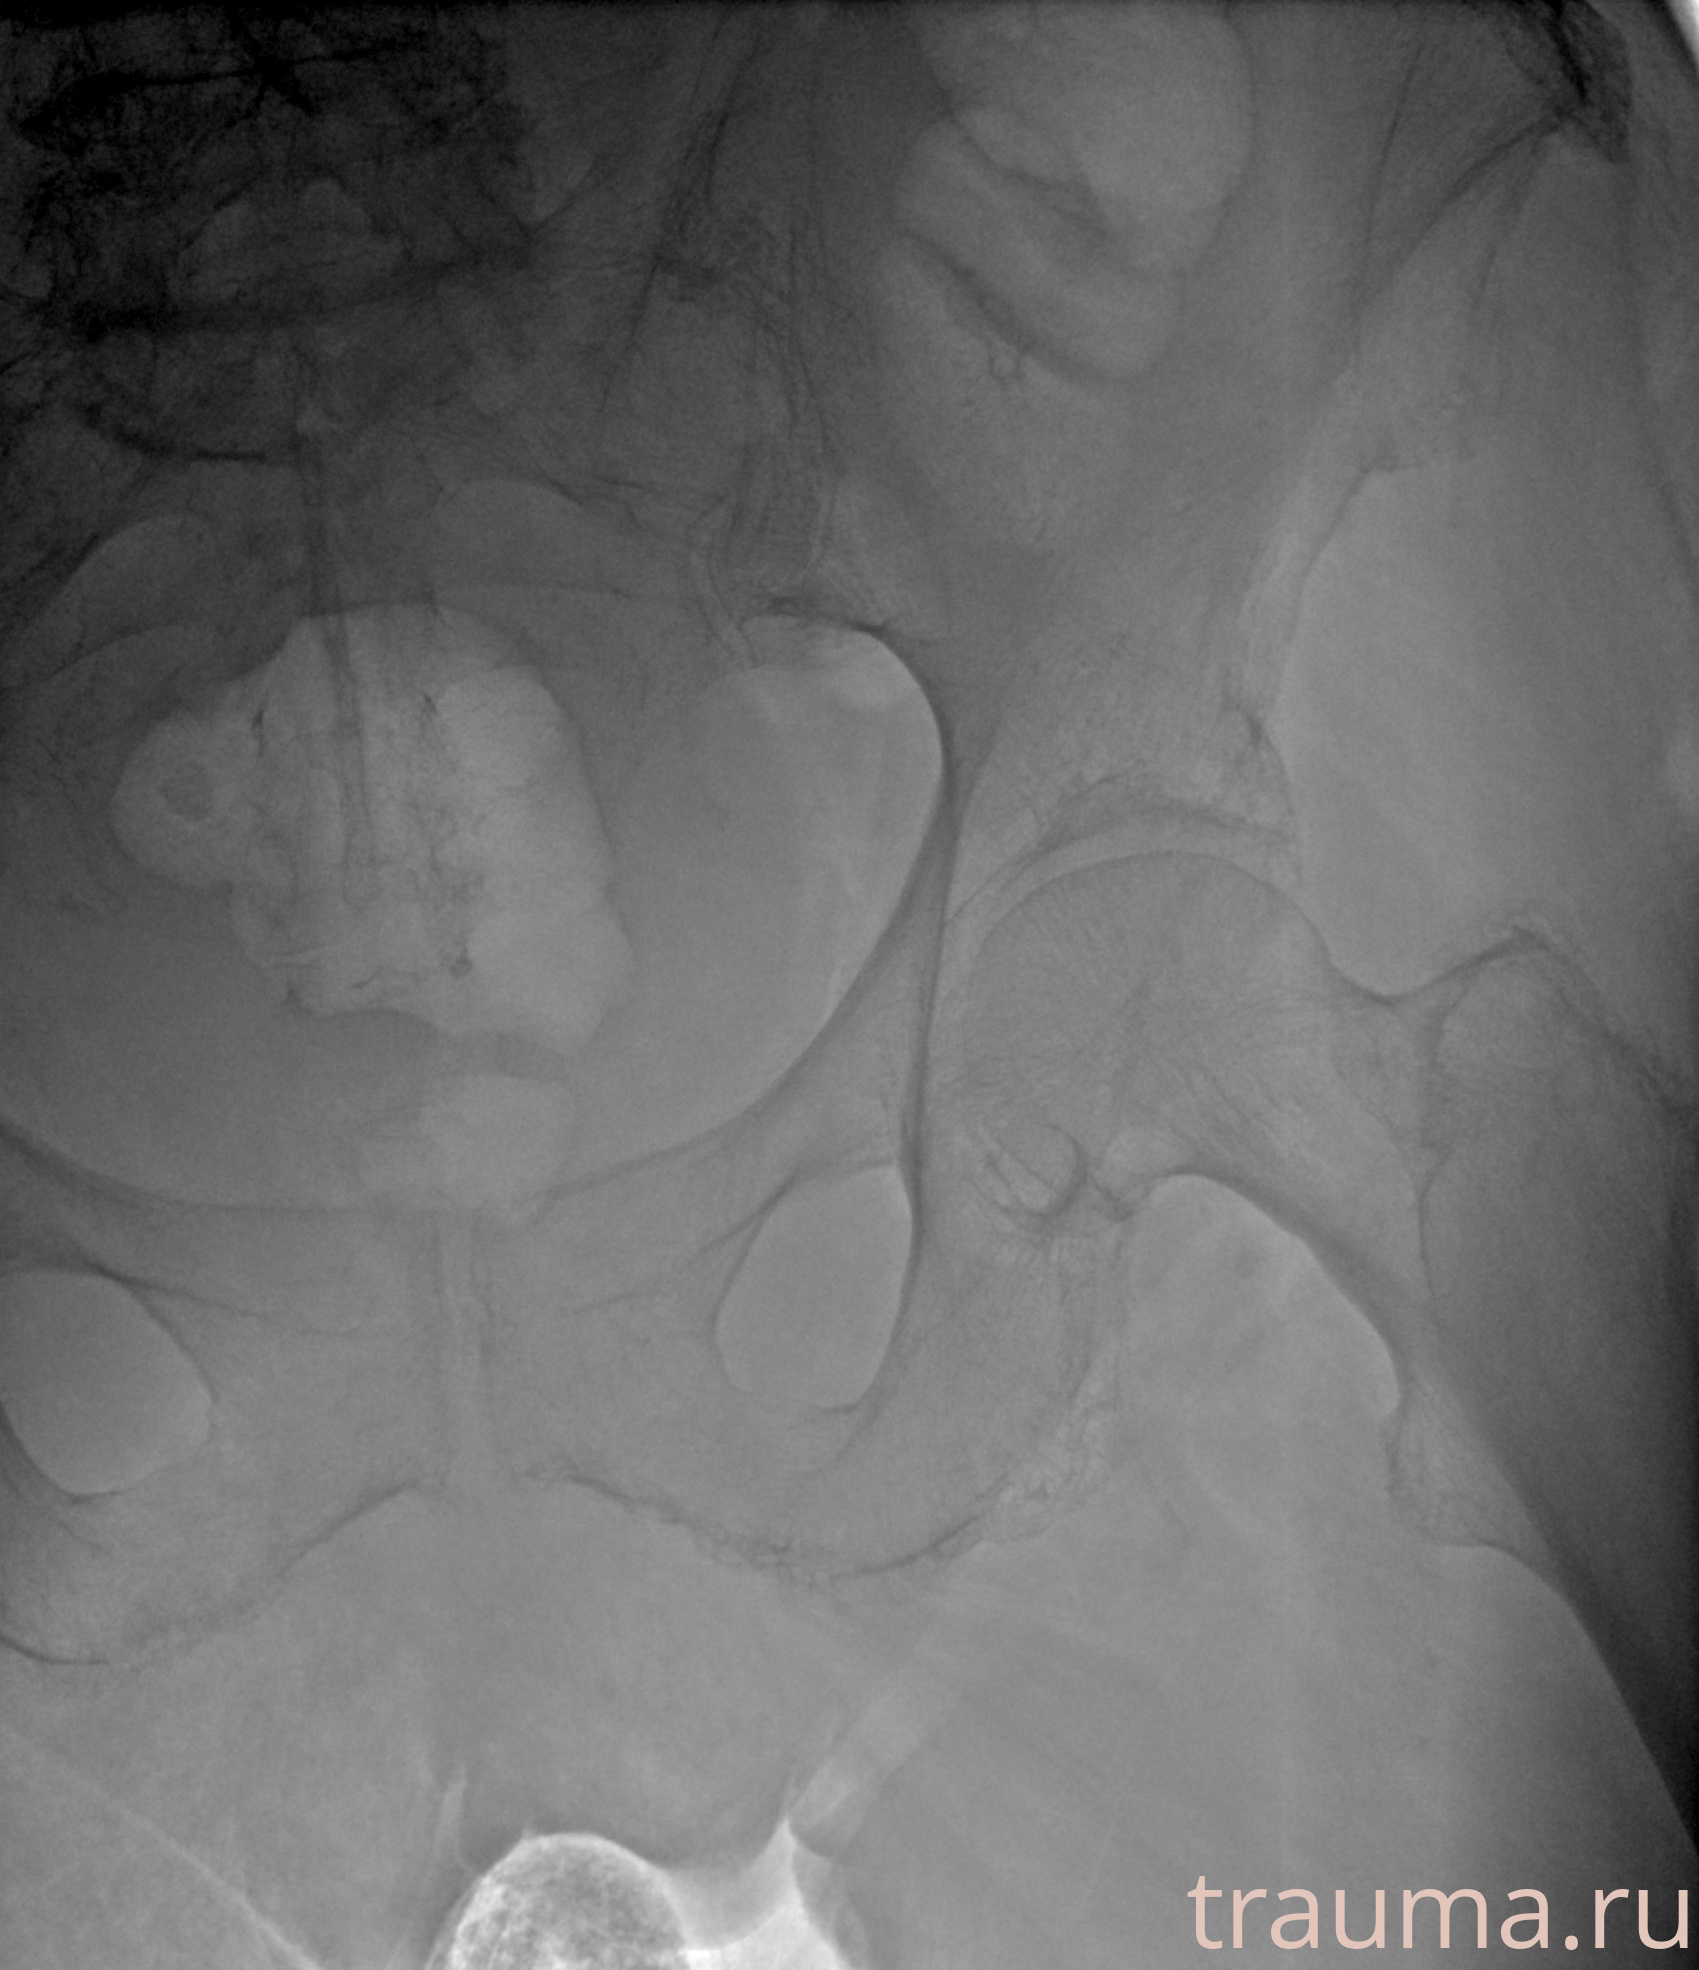

Рентгенограммы

Рентген на дому: по вашему адресу приезжает врач-рентгенолог, травматолог-ортопед с мобильным рентгеновским аппаратом, проводит диагностику травмы или заболевания, делает необходимые рентгенограммы, дает рекомендации по дальнейшему лечению. Получить качественные снимки в домашних условиях возможно благодаря уникальной методике, разработанной МосРентген Центром для института  Склифосовского